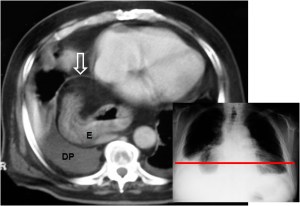

SIGNO DEL ÁREA DESNUDA

Cuando en la TC vemos líquido en situación dorsal al hígado (flecha), éste se encuentra en la cavidad pleural, ya que el líquido intraperitoneal no puede acumularse en esta zona debido a que el peritoneo se repliega sobre la cúpula hepática sin llegar a cubrir la parte posterior del hígado, es decir, que no hay cavidad peritoneal por detrás del hígado y, por tanto, la ascitis no puede ocupar este espacio.

En esta imagen también está presente, lógicamente, el Signo de la interfase.

En la imagen correspondiente a ascitis que presentamos en el signo anterior, observa cómo se respeta la zona posteromedial del hígado.

SIGNO DE LAS CRURAS O DEL PILAR DIAFRAGMÁTICO DESPLAZADO

Cuando en la TC vemos que las cruras diafragmáticas están desplazadas lejos de la columna por líquido, éste está situado en la cavidad pleural (flecha). El líquido intraabdominal, a diferencia del derrame pleural, se sitúa lateral y anterior a las cruras.